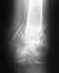

Re: Несращение огнестрельного перелома н/3 бедра

Что делать - мы бы малоинвазивно убрали пластину и сделали бы закрытый интрамедуллярный остеосинтез с блокированием. Исправилась бы ось. Нагрузка без ограничений сразу. Никаких пластик, ни на питающей ножке, ни и без нее, не нужно.

Если делать пластику, оставляя ту же пластину, это сопряжено с много большими рисками всяких неприятностей.